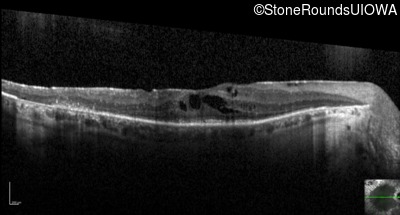

Optical Coherence Tomography - Right - 20/50

Exemplar / OCT Stack

OCT Stack